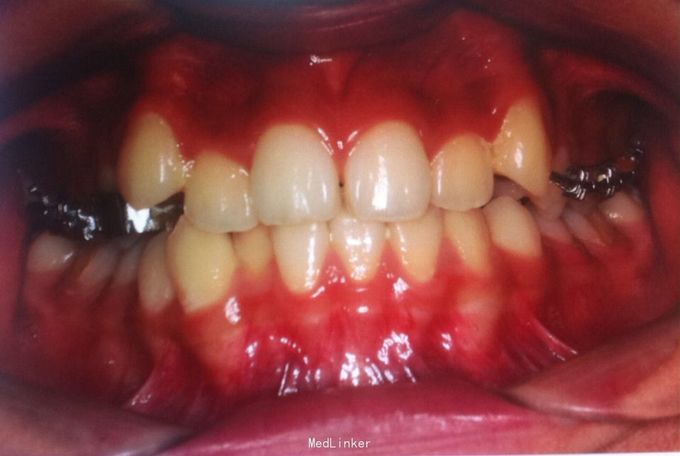

恒牙期 口内见摆式矫治器 左侧磨牙近中关系,右侧中性关系 前牙覆合覆盖正常 中线不正 上下牙列拥挤 张口度正常 关节有弹响 开口型异常

安氏三类 拆除摆式矫治器,清洁牙面,直丝弓矫治器,排齐整平上下牙列,矫治后磨牙中性关系,前牙覆合覆盖正常,维持现有面型